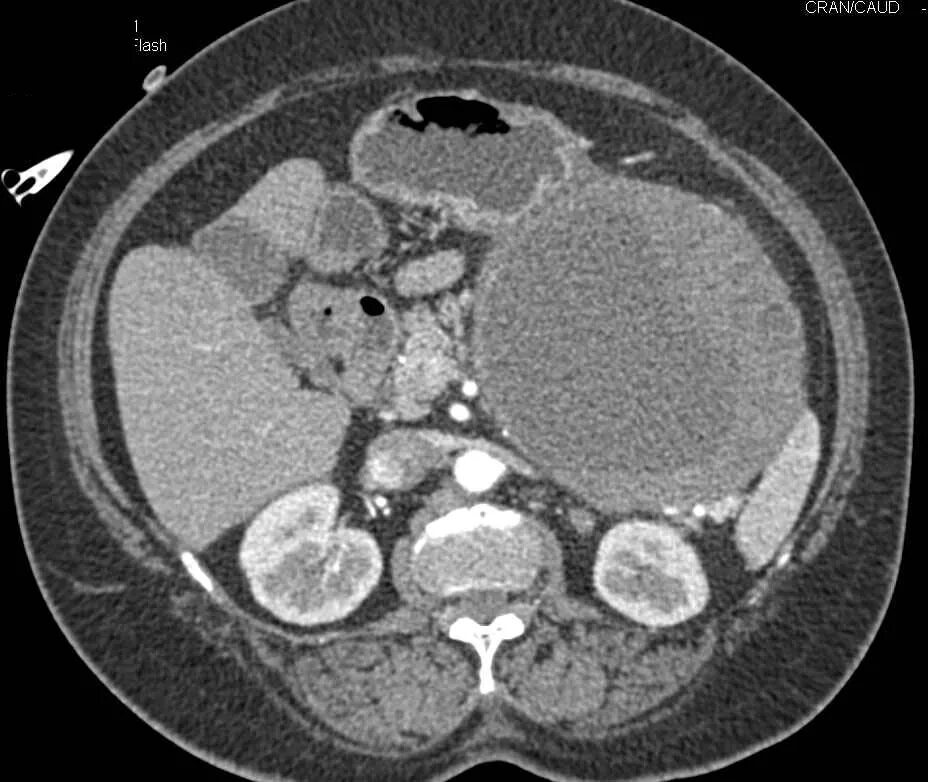

Рак прямой кт